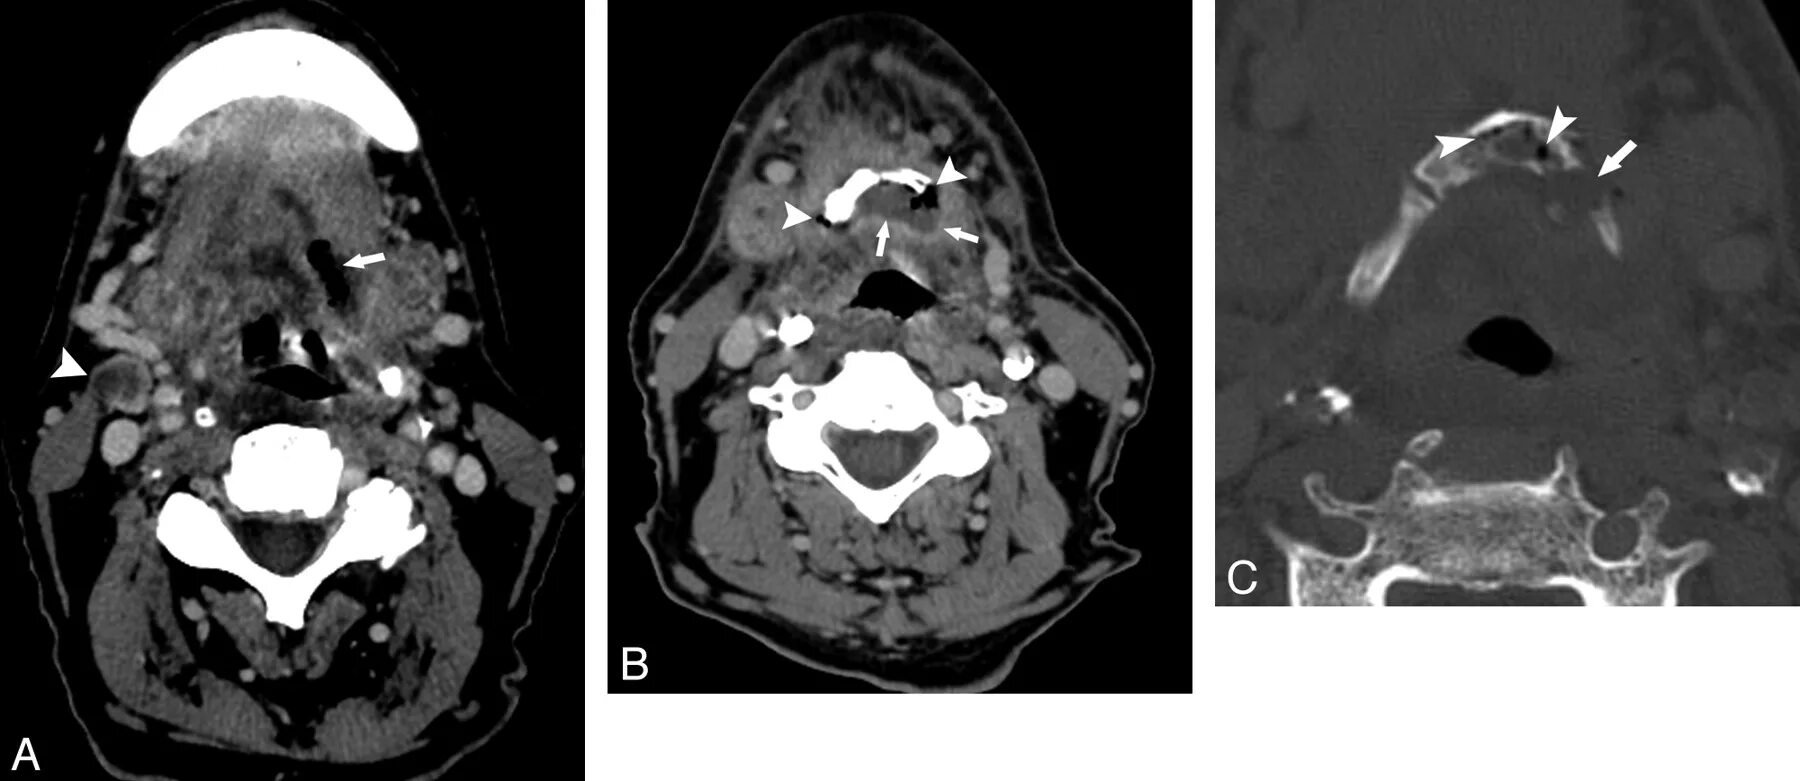

Ct search